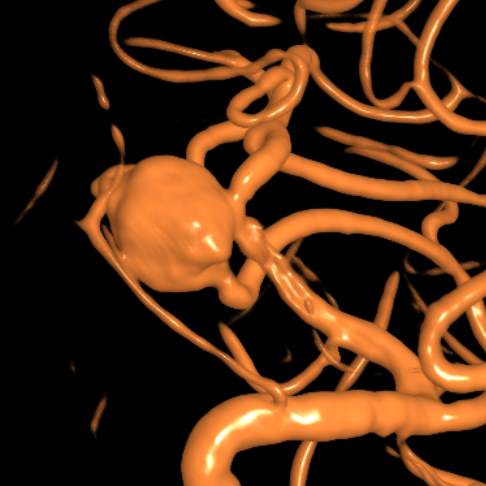

粗大分支从破裂瘤体上发出来,急性期能单纯致密栓塞吗?

病史:中年女性,新冠感染,颅内动脉瘤破裂,Hunt-Hess 4级

最终,动脉瘤瘤体致密栓塞,各个分支保留良好